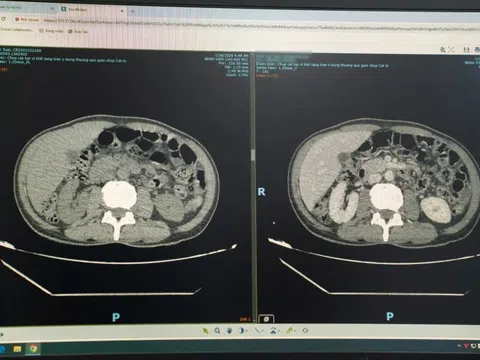

Ho là triệu chứng thường gặp ở trẻ em, đặc biệt là trẻ nhỏ. |